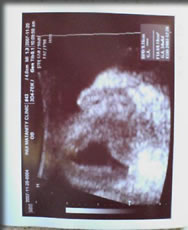

葉羽 2007年12月4日の午後2時頃「妊婦日記」のちぃな嬢に、めでたく第一子誕生!! 病室に戻るなり撮影されました緊急画像がリアルタイムで到着! 「岸波通信」読者の皆様にだけお届けする、できたてホヤホヤのお子様写真。